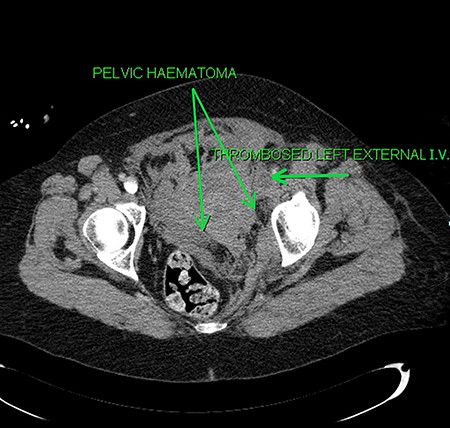

Axial sections of the CT scan showing the thrombosed external iliac vein (I.V.) and the pelvic haematoma.